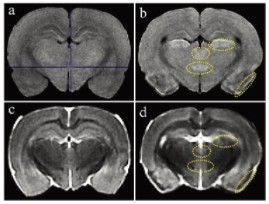

圖1顯示了T1和T2加權(quán)MRI圖像。與對照組相比, 匹羅卡品處理的動物在梨狀皮質(zhì)、丘腦外側(cè)核、丘腦室周后核和大腦下丘腦后核的T1加權(quán)圖像顯示出高T1信號(圖1a和b)。在匹羅卡品處理的動物的T2加權(quán)圖像中,與對照組相比,在梨狀皮質(zhì)觀察到低T2信號,對應(yīng)于高T1信號區(qū)(圖1c和d)。其他3個高T1信號區(qū)的T2信號強度與對照組相當(中等強度)(圖1c和d)。